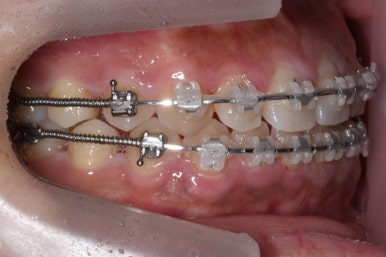

위 사진은 부산치아교정치과에 내원하셨을 대 당시의 입안 모습입니다.

치아들 사이에 전반적으로 틈이 많이 있는 상태입니다.